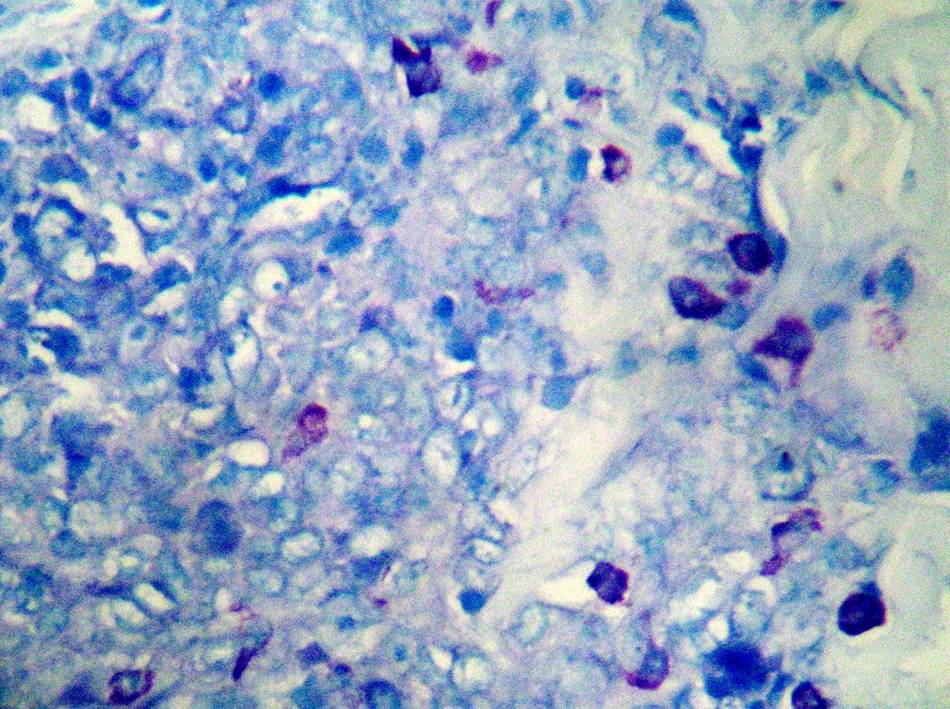

【產(chǎn)品介紹】肥大細胞(Mast?Cell)來(lái)源于未分化的間充質(zhì)細胞,近年來(lái)有人認為可能來(lái)自胸腺和骨髓。正常多見(jiàn)于小血管周?chē)?,一般在結締組織中都含有少量的肥大細胞,也常見(jiàn)于支氣管周?chē)鸵鹊男∪~間導管周?chē)?,而在腸系膜的小血管周?chē)加写罅康姆蚀蠹毎?。肥大細胞較一般細胞大,直徑約20~30μm。呈圓形或橢圓形;胞核較小,圓形;胞質(zhì)內充滿(mǎn)粗大并具有異染性的圓形嗜堿性顆粒。

【染色結果】肥大細胞顆粒含有肝素和組織胺等,這些屬于硫酸酯,呈異色性。因此,用易染性染料甲苯胺藍可以使其呈異色性的紅紫色。